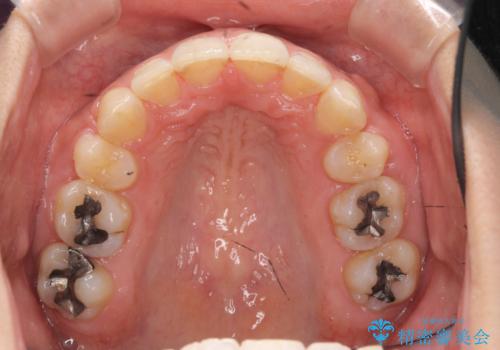

Eラインを整える治療 前歯を引っ込めます

年齢の割に歯が動きにくかったこともあり、また、追加で抜歯して結果として時間がかかってしまいました。口元が大きく下がり、結果には満足していただけました。

横顔が大きく変わり、満足していただけました。